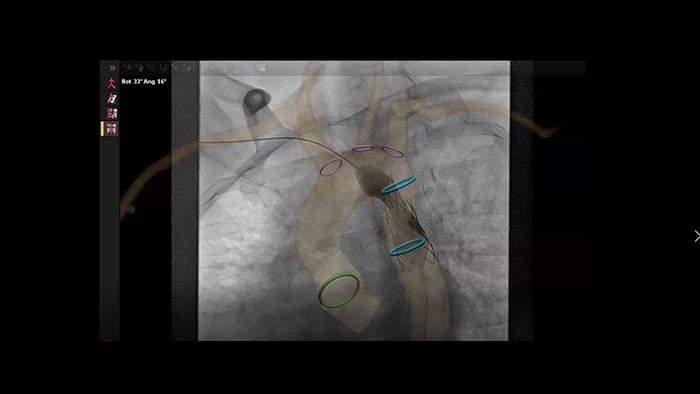

Anatomical landing zone marking on TSM Pro

Automatic vessel analysis from rotational angiography with SmartCT

SmartCT live guidance